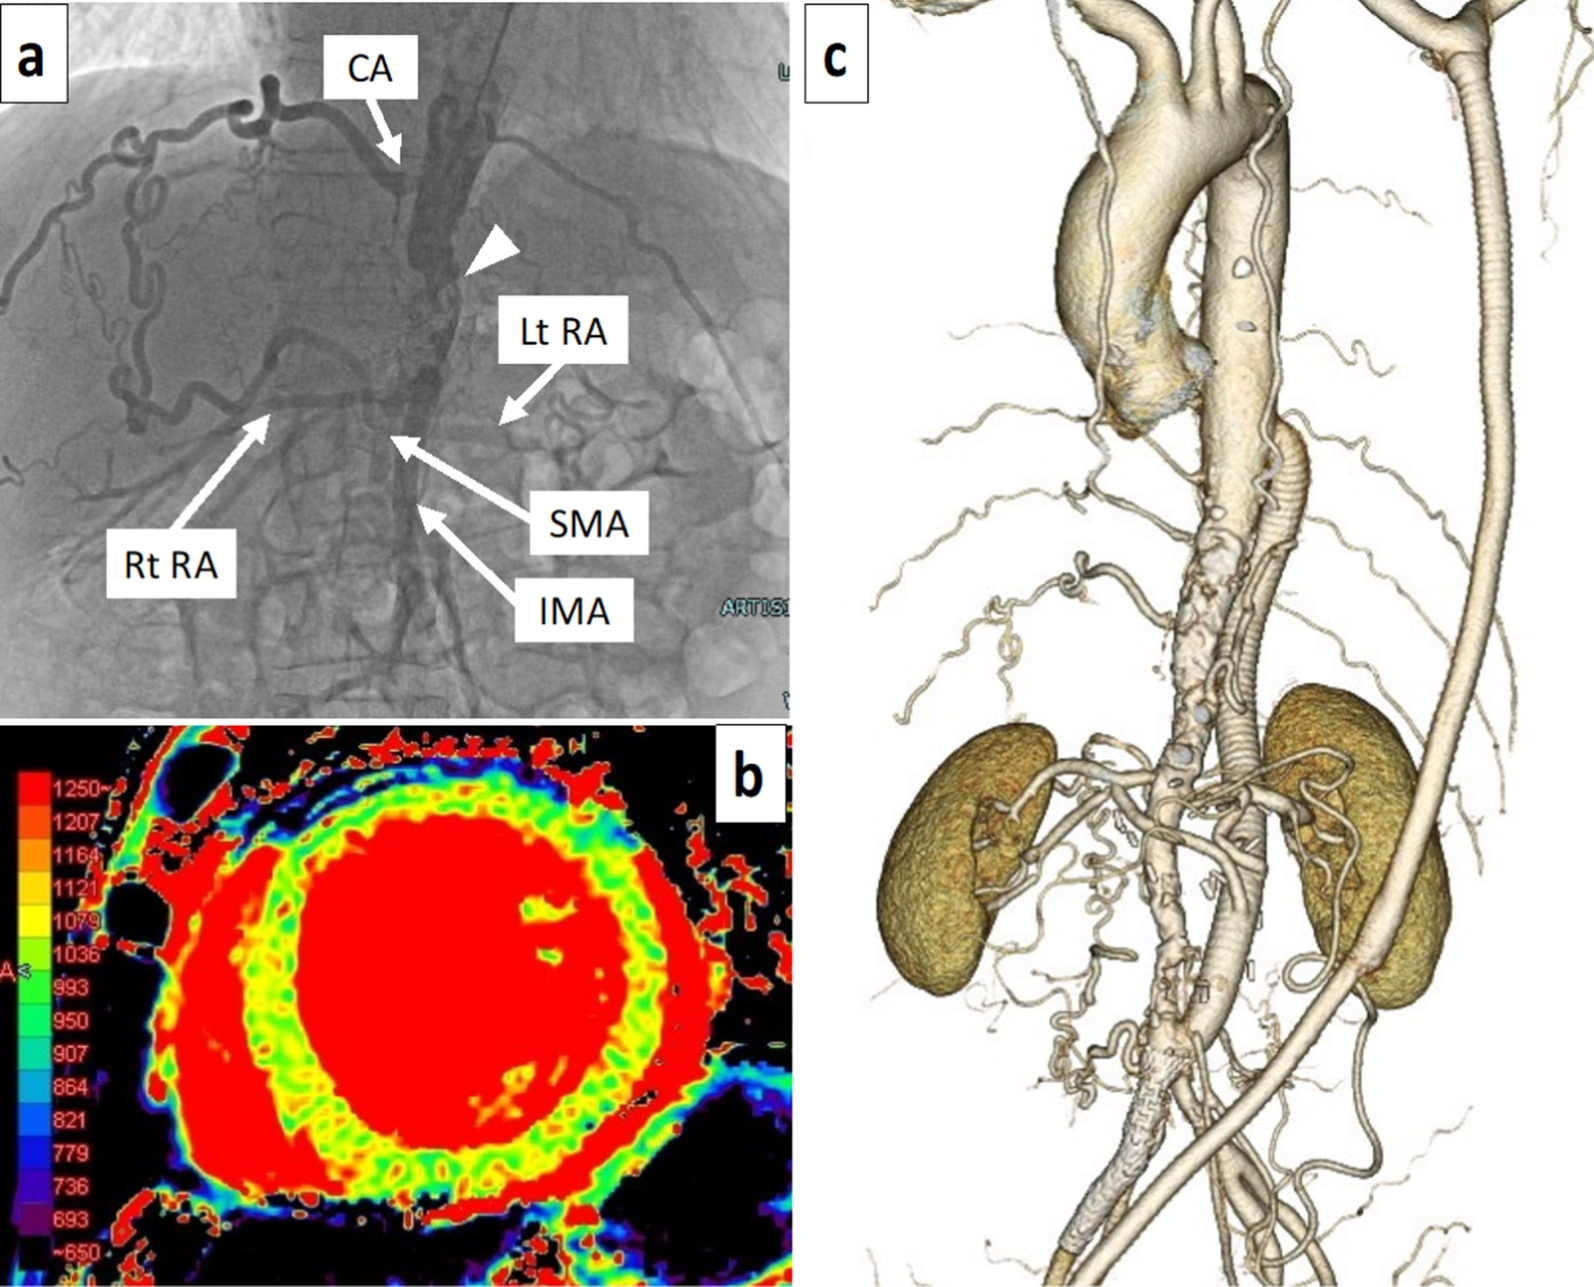

Fig. 2

Preoperative aortography, magnetic resonance imaging, and postoperative computed tomography. a Aortography showing the superior mesenteric artery (SMA) imaged by the well-developed collateral circulation from the celiac artery (CA). Bilateral renal arteriography was delayed. Severe stenosis is observed in the epigastric aorta of the renal artery (arrowhead). b T1 mapping images on visceral MRI shows a slight increase in the T1 value of the left ventricular wall and no fibrosis progression on the left ventricular wall. c Postoperative 3D-CT showing that the descending thoracic aorta-abdominal aorta bypass and bilateral renal artery bypass were patent